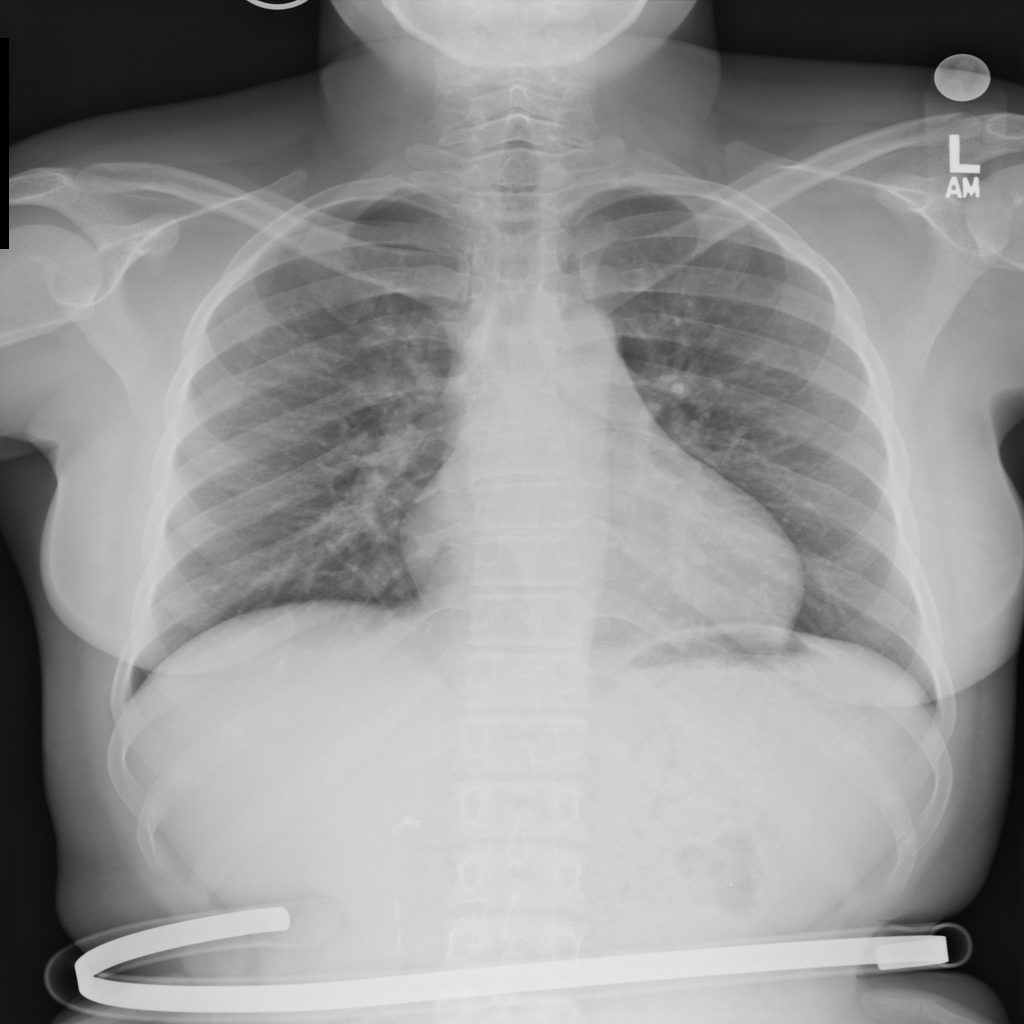

PAT-5092 · IMG-004Cardiomegaly

PAT-5092 · IMG-004

AP